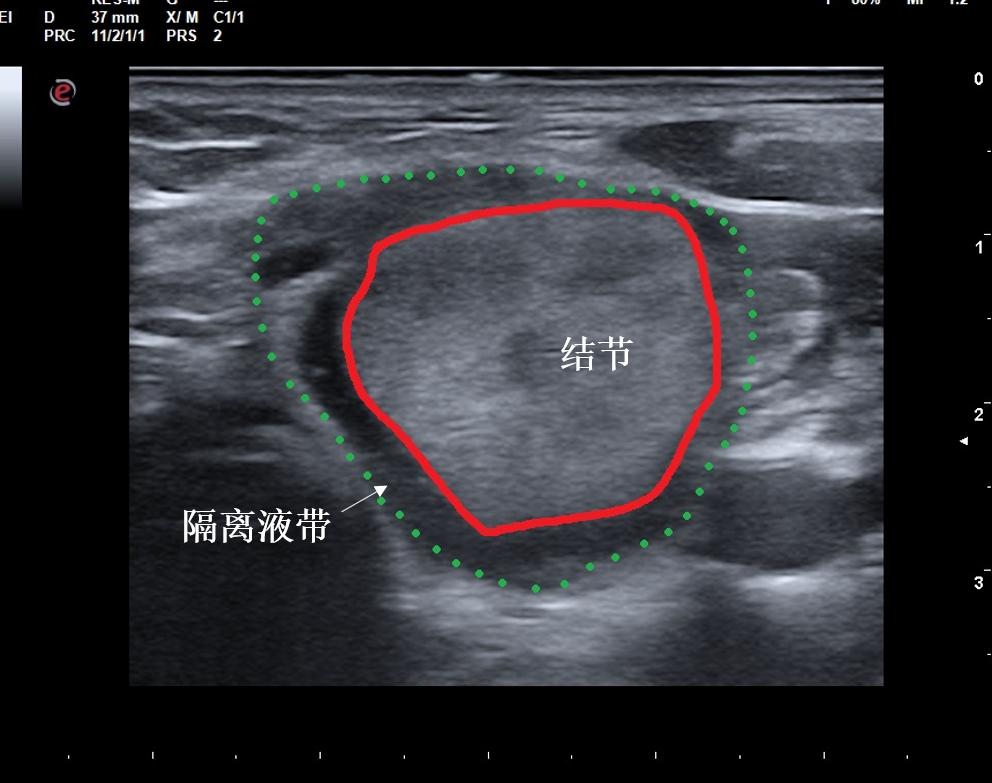

图为微创消融手术中,用隔离液带(红线与绿线之间区域)完全包裹甲状腺结节。

既让手术全程无痛,又很好地保护了周围正常结构不受热损伤,极大减少了并发症的发生。